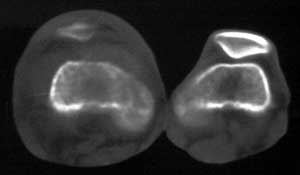

男56涨疼5-6月

右股骨下端包绕股骨见巨大软组织肿块,密度部俊,周围见瘤骨,下端骨皮质侵蚀变薄,骨质周围无骨膜反应, 考虑右股骨软骨肉瘤。

右股骨下段周围软组织肿块伴钙化,相邻股骨骨皮质受累,考虑软组织来源恶性病变

右股骨下段骨肉瘤,软组织内瘤骨,软组织肿块。